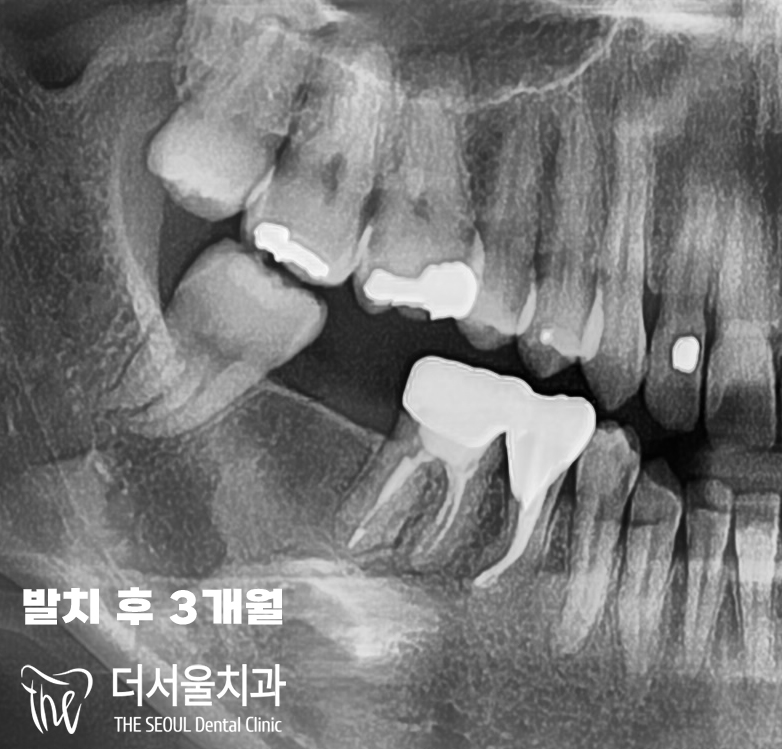

파노라마 엑스레이 촬영 결과,

크라운 밑으로 심하게 썩어서

뿌리까지 염증 이 발생한 어금니를

찾아볼 수 있습니다.

이미 돌이킬 수 없을 정도로

심했기 때문에

발치 후 임플란트를 하는 게

환자분에게 더 나은 상황이었습니다.

『3 Months later…』

그렇게 47번 어금니 발치 후

3개월이 흐른 뒤,

다시 성남 치과 에 찾아오셨습니다.

환부 확인 결과, 잘 아물게 되면서

임플란트 수술이 가능해졌습니다.